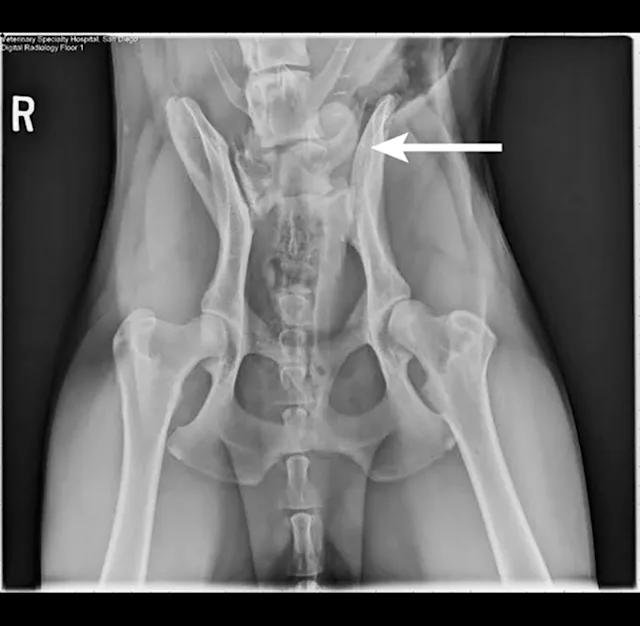

Survey radiography of the lumbar spine, pelvis, and hips is recommended. Common abnormalities identified in patients with LS disease include vertebral spondylosis, sclerosis of the vertebral end plates, and collapsed L7-S1 disk space. Stress radiography may exacerbate a lumbosacral step, which can further aid in diagnosis. Radiographs are also recommended to help rule out metastatic disease, diskospondylitis, trauma, or luxation (Figures 1-3).

Figure 1

Right lateral radiograph of a dog demonstrating L7 fracture. Images courtesy of Dr Tammy Stevenson.